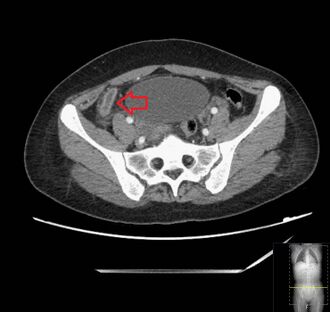

_(Radiopaedia_154713-127660_Axial_1).jpg)

Where it is readily available, computed tomography (CT) has become frequently used, especially in people whose diagnosis is not obvious on history and physical examination. Concerns about radiation tend to limit use of CT in pregnant women and children, especially with the increasingly widespread usage of MRI.[49][50]

The accurate diagnosis of appendicitis is multi-tiered, with the size of the appendix having the strongest positive predictive value, while indirect features can either increase or decrease sensitivity and specificity. A size of over 6 mm is both 95% sensitive and specific for appendicitis.[51]

However, because the appendix can be filled with fecal material, causing intraluminal distention, this criterion has shown limited utility in more recent meta-analyses.[52] This is as opposed to ultrasound, in which the wall of the appendix can be more easily distinguished from intraluminal feces. In such scenarios, ancillary features such as increased wall enhancement as compared to adjacent bowel and inflammation of the surrounding fat, or fat stranding, can be supportive of the diagnosis. However, their absence does not preclude it. In severe cases with perforation, an adjacent phlegmon or abscess can be seen. Dense fluid layering in the pelvis can also result, related to either pus or enteric spillage. When patients are thin or younger, the relative absence of fat can make the appendix and surrounding fat stranding difficult to see.[52]